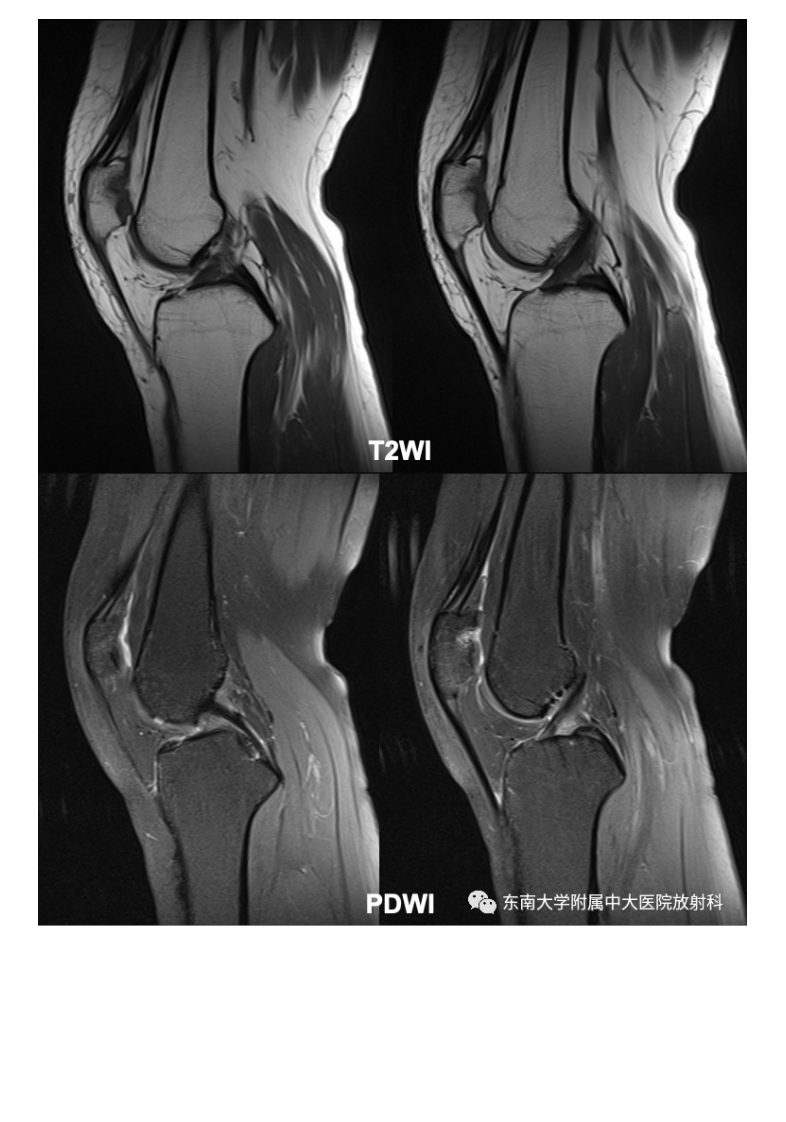

20210506_3【晨读结果公布】2021.05.06肌骨系统疾病——髌骨软化症.pdf